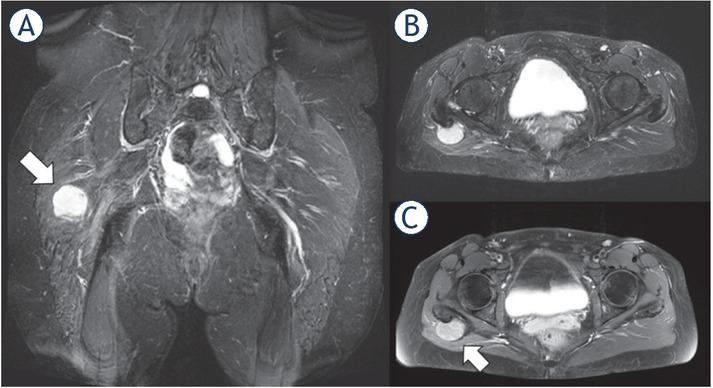

Figure 3